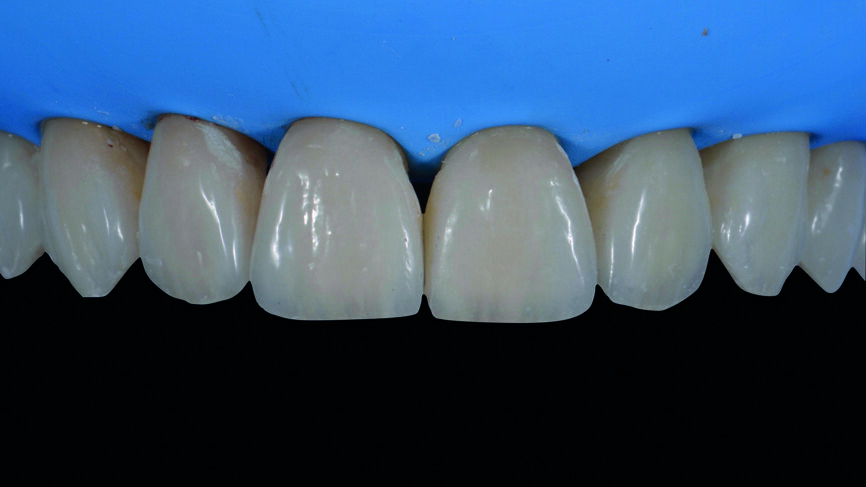

Fig. 16e : Facettes in situ avant la finition et le polissage.

Fig. 16f : Résultat final immédiatement après le retrait de la digue en caoutchouc.

Le clinicien et la patiente ont décidé subjectivement un scellement des facettes en céramique feldspathique en raison des légères différences dans la longueur des incisives centrales des deux jeux. Les procédures adhésives ont suivi (Figs. 16a–f) et des photographies intra-orales et extraorales ont finalement été prises une semaine plus tard (Figs. 17a–e).